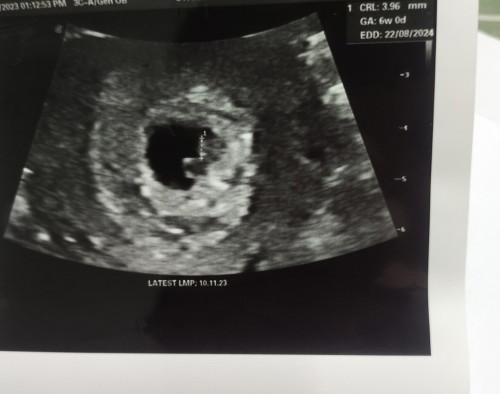

Hi assalamualaikum saya nk tanya ibu2 dalam ni .. sebelum tu ,ni kandungan yang ke 3.. kiranya ni anak ke 3.. tapi yg ni mcm lain sikit rasa pregnant dia.. saya cepat lapar.. macam mana ya nk ckp .. normal ke lapar yg teruk sangat ? Contoh saya sarapan pukul 9pg.. 9.30 pagi dah lapar balik 😂 tapi saya makan kerap sangat.. saya macam tertanya-tanya saya ni pregnant twin ke 😂 tapi bila saya check up 7 week haritu di swasta, doc scan ada 1 je baby.. alhamdulillah sihat cuma kecik seminggu 🤭 kiranya baru 6 week.. saya ingat nk bukak buku 10 week or 12 week tapi rasa2 kena marah tak kalau saya bawak scan pregnant 6 week ni di KK? Dulu anak2 sebelum ni 3 hari sebelum g KK untuk bukak buku,saya akan ke swasta UTK scan & confirm pregnancy.. saya memg bawak siap2 scan swasta ni ke KK Sebb tak nk urine test (utk confirm pregnant dari KK) 😂 malas nk tunggu lama2 di KK .. ada tak pengalaman ibu2 yg pregnant twin? Saya takde keturunan twin tapi teringin twin ,mana tahu tiba2 rezeki pregnant twin kan 😂 tapi tak mungkin lah kan Sebb scan 1 je baby.. syukur Alhamdulillah dia sihat.. cumanya pelik saya lapar tahap teruk sangat .. muntah2 tak sangat cuma rasa mual je ,tak boleh tgok makanan & pening kepala dari pagi sampai malam tapi xde lah teruk .. malam je saya tak tahan pening kepala teruk sangat... Dan saya cepat mengah & letih ,risau pulak masa bukak buku tu berat sangat pulak nanti misi bising2 setiap month berat naik banyak ..#ingintahu